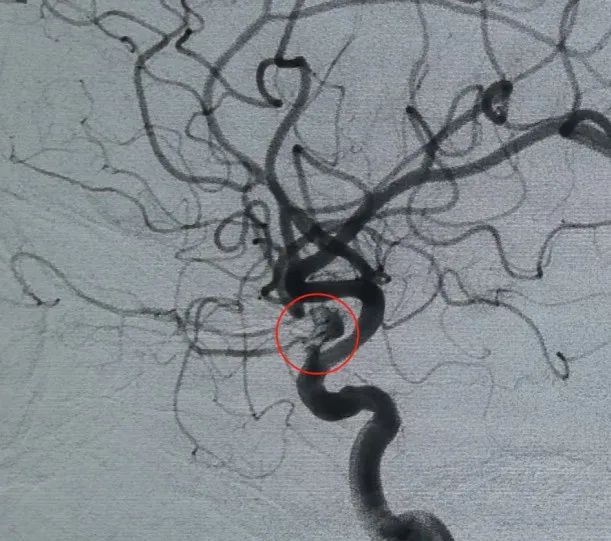

Diagnosis: Left internal carotid artery C6 segment ophthalmic artery aneurysm

Vascular access was established via femoral artery puncture, and a Perdenser® 6 mm × 20 cm 3D coil was first deployed to form a basket, achieving stable wall apposition and providing secure intrasaccular support. This was followed by the insertion of a Perdenser® 6 mm × 15 cm 3D coil to disrupt blood flow within the lobulated daughter sac.

A Perfiller® 3 mm × 6 cm expansible coil and a Perfiller® 3 mm × 2 cm expansible coil were then placed to complete neck occlusion. Subsequently, a Nuva® Flow Diverter (TJED-D-5.0-16) was delivered and deployed across the aneurysm neck. Follow-up angiography in both anteroposterior and lateral views confirmed excellent coverage, good wall apposition, and clear radiopacity, with marked contrast stagnation.